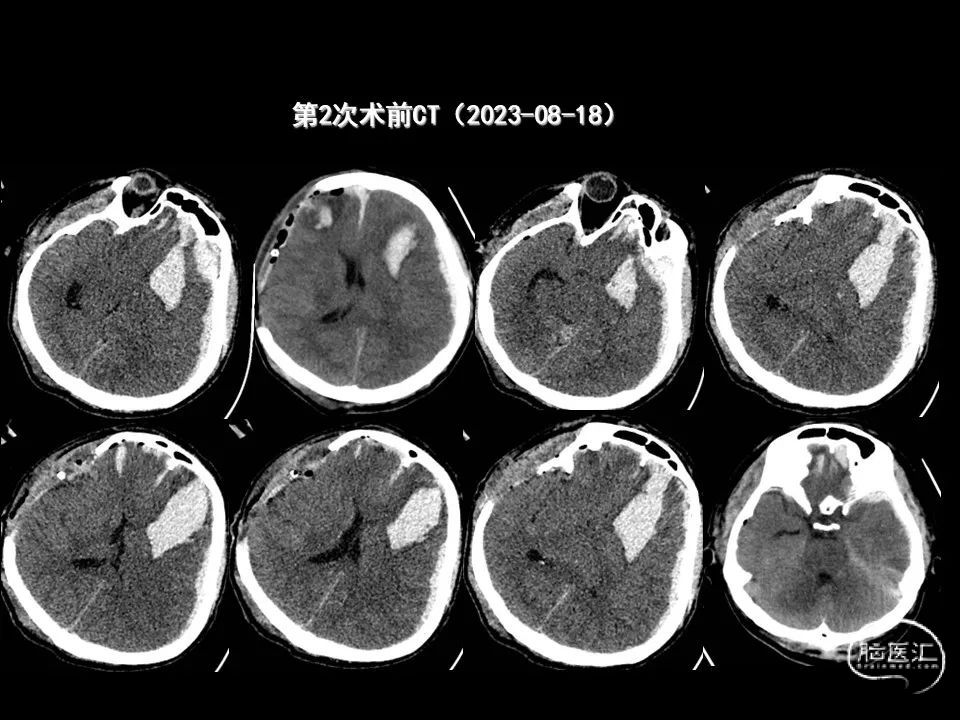

今天为大家分享的是《监测有道丨颅脑创伤-神经重症周刊》第338期,由海南省人民医院朱蔚林教授带来的:2例脑出血微创手术,欢迎阅读、分享。